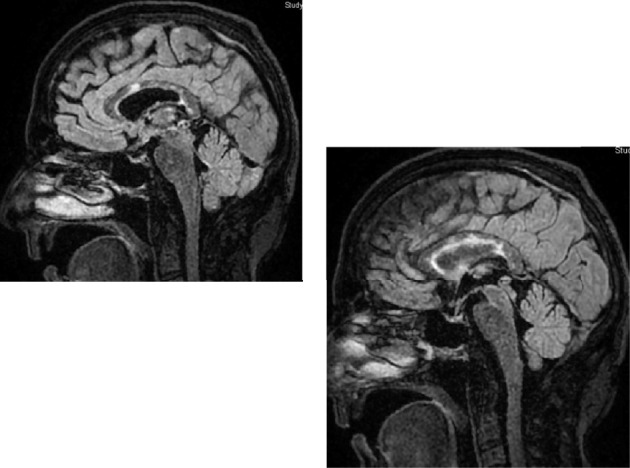

我们报告一个55岁的右撇子女性的病史甲状腺功能减退和胃旁路手术。患者最初表现为认知障碍、头晕和步态不稳。尽管进行了普通的中风检查,但她的症状在2天内迅速恶化,导致随后的住院和复杂的诊断过程,发现了Susac综合征——一种罕见的影响大脑微血管、视网膜和耳蜗的自身免疫性疾病。患者的治疗包括皮质类固醇、IVIG、霉酚酸盐和环磷酰胺的积极免疫抑制。患者反应良好,病情逐渐好转,出院回家。本病例强调了Susac综合征的诊断挑战和管理策略。

We report the case of a 55-year-old right-handed female with a medical history of hypothyroidism and gastric bypass surgery. The patient initially presented with cognitive impairment, dizziness, and unsteady gait. Despite an unremarkable stroke workup, her symptoms progressed rapidly within 2 days, leading to subsequent admissions and a complex diagnostic journey revealing Susac syndrome-a rare autoimmune disorder affecting the brain's microvasculature, retina, and cochlea. The patient's treatment involved aggressive immunosuppression with corticosteroids, IVIG, mycophenolate, and cyclophosphamide. The patient responded well and had progressive improvement, with discharge to home. This case highlights the diagnostic challenges and management strategies for Susac syndrome.